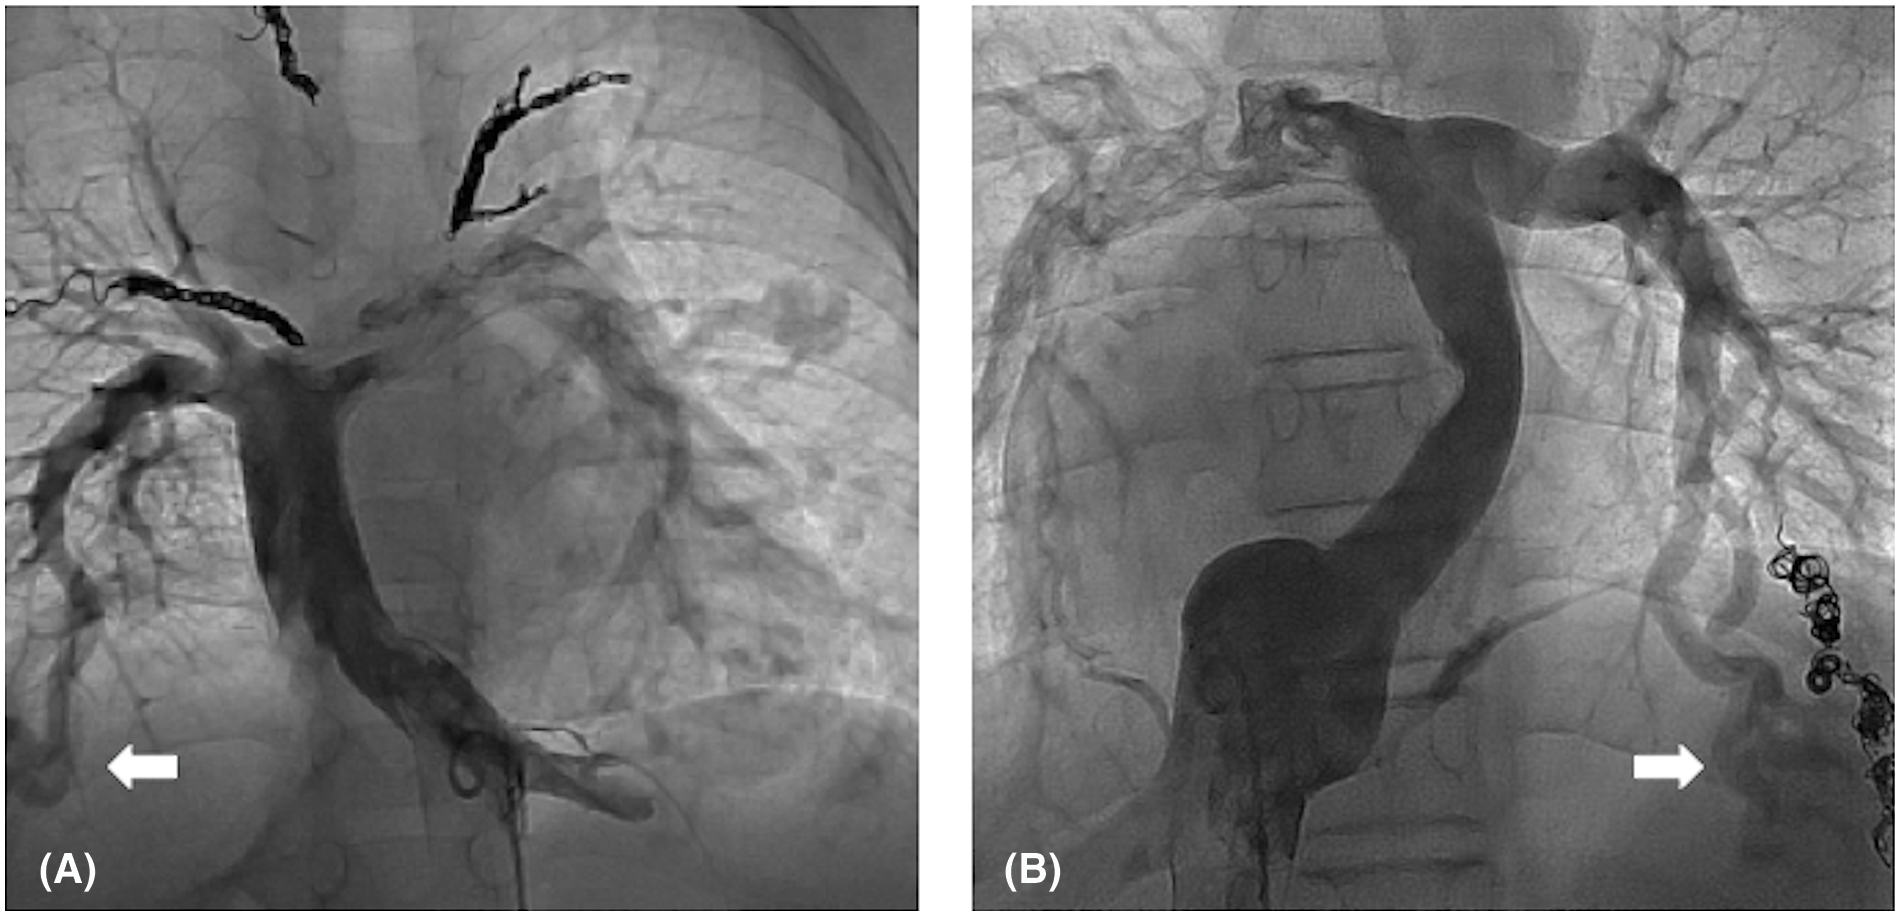

TCPC was performed in 20 patients. The median follow-up period after TCPC was 8.1 years. Adverse events occurred in seven patients, including death in one, intervention for pulmonary arteriovenous malformation (PAVM) in three (coil embolization in two and hepatic vein redirection in one), and surgical intervention for the development of PVO in three. The adverse event-free survival rate after TCPC was 80% at 5 years and 69% at 10 years. The detailed data of patients’ data who developed adverse events after TCPC are shown in Table 4. Patient 1 had right PVO and died suddenly at home 3 years after TCPC. Patients 2 and 3 developed severe hypoxia due to PAVM after TCPC and underwent coil embolization. Both of these patients had right isomerism without inferior vena cava (IVC) interruption. In Patient 2, angiography after TCPC showed right-dominant IVC blood flow and bilateral PAVM. In Patient 3, angiography showed left-dominant IVC blood flow and left-sided PAVM (Fig. 7). Patients 4 and 5 developed PVO due to compression of the extracardiac conduit. They underwent conduit replacement 3 and 5 months after TCPC, respectively and the PVO was relieved. Patient 6 had intracardiac TAPVC and PVO that developed secondary due to membranous obstruction of the pulmonary venous orifice. The patient underwent a surgical resection of the membrane 1 year after TCPC, and the PVO was successfully relieved. Patient 7 had left isomerism with IVC interruption. He developed severe hypoxia due to PAVM and redirection of the hepatic vein to the azygous vein was performed 14 years after TCPC. The hemodynamic characteristics before TCPC were compared between patients with and without adverse events after TCPC (Table 5). The B-type natriuretic peptide (BNP) concentration was significantly higher in patients with than without adverse events (p = 0.02).

Figure 7: IVC angiography in patients who developed PAVM after TCPC. (A) Bilateral PAVM in a patient with right-dominant IVC blood flow. (B) Left PAVM in a patient with left-dominant IVC blood flow. White arrows indicate PAVM